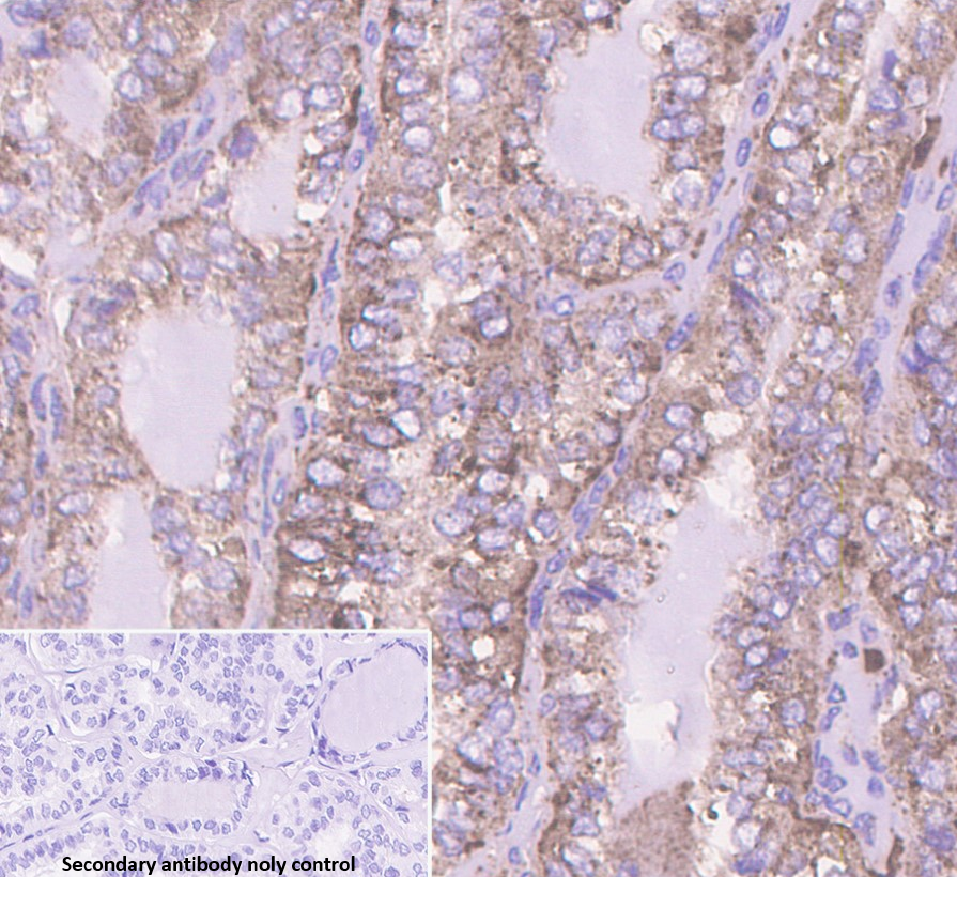

Cellular localization: cytoplasm

Tissue: paraffin section

CathespinD is an intracellular lysosomal enzyme widely present in cells, which has a certain correlation with tumor infiltration and metastasis, and is overexpressed in breast cancer and some other malignant tumors. It is overexpressed in breast cancer and some other malignant tumors. Studies have shown that CathespinD is often expressed in ER-negative breast cancers, and is associated with the proliferation and metastasis of breast cancer.

Cathepsin D antibody reagents can specifically bind to Cathepsin D molecular antigens. Immunohistochemistry kits containing Cathepsin D antibody reagents are suitable for the auxiliary diagnosis of breast cancer.